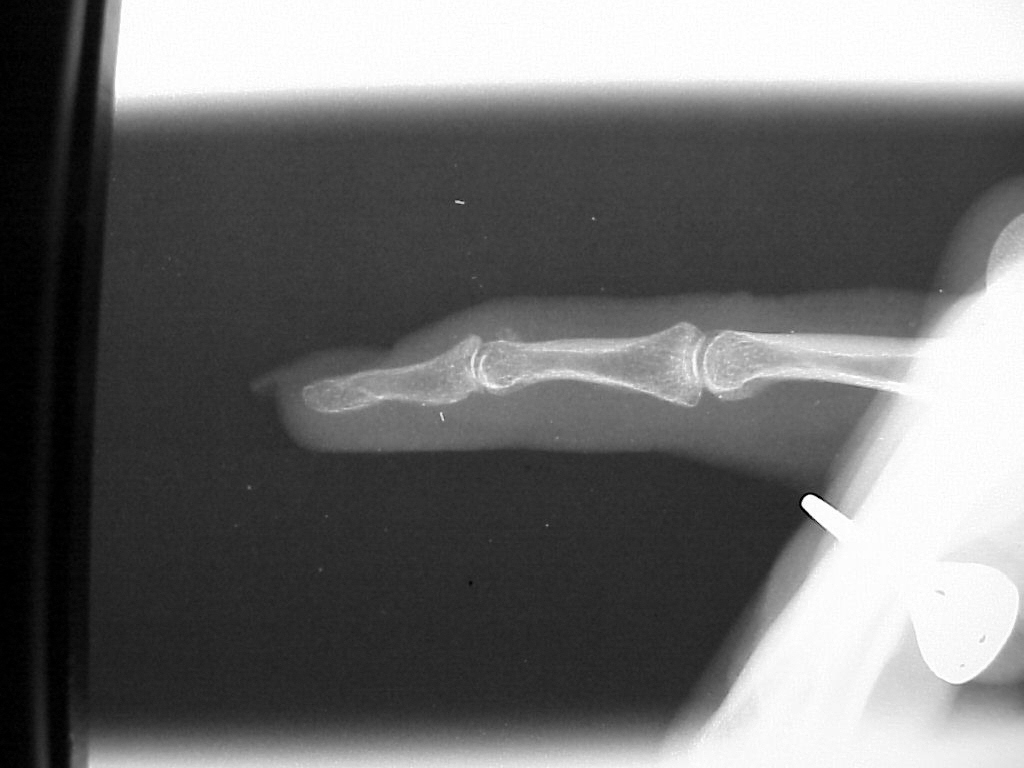

Case 3

Acute mallet fracture treated with percutaneous

pinning: proximal pin stabilizes the fracture

fragment, longitudinal pin maintains distal phalanx

position. |

| Thermoplastic bonding of the protruding ends: appearance at one month. |